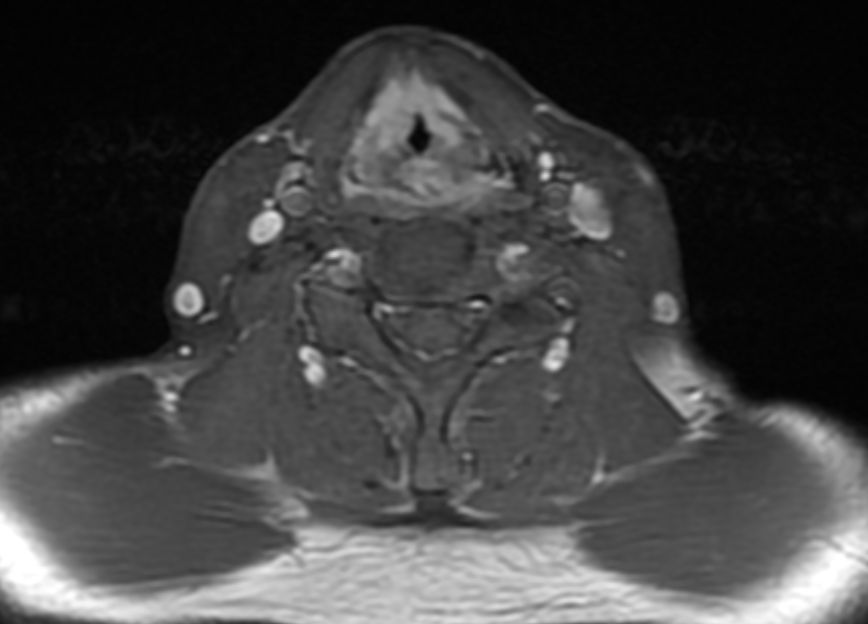

MRT: supraglottisch T3 No |

57-jähriger Mann mit langjährigem Alkohol- und Nikotinabusus. Seit 6 Monaten Schluckbeschwerden. Jetzt zunehmende Kachexie. MRT: Ausgedehntes supraglottisches Larynxkarzinom mit Schildkrorpel-Infiltration. Kehlkopfteilresektion mit ND. Histologie: unverhornendes Plattenepithelkarzinom, V0 R1 G1 - 2 Stadium post OP: pT3 pN0 (0/7) M0 | ||